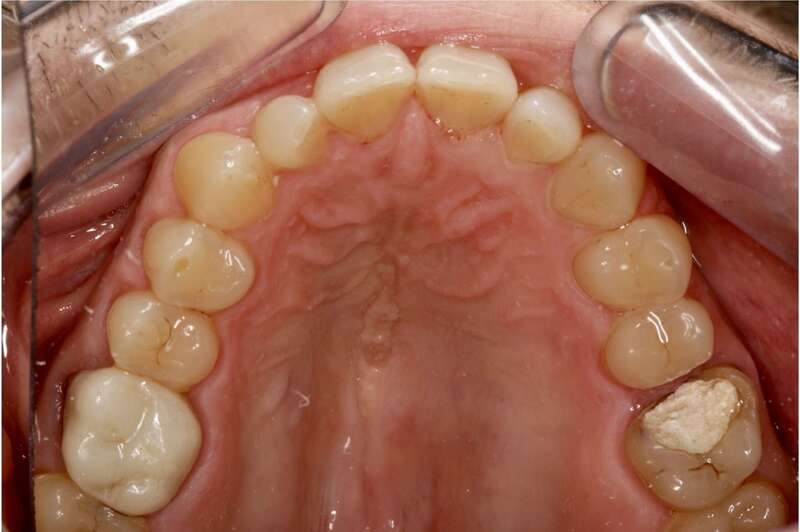

Situation clinique initiale : le patient se présente avec une obturation provisoire sur la dent 26 avec douleur.

Situation clinique initiale